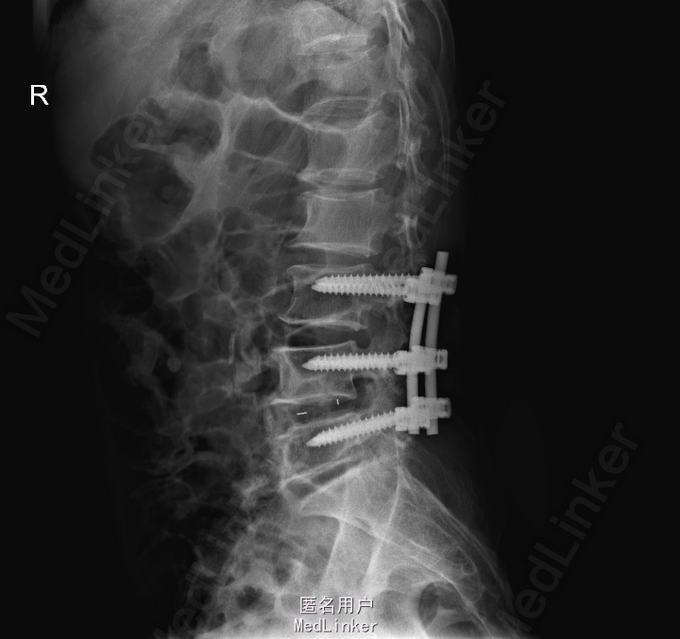

查体:左侧小腿外侧、足背感觉减退,右侧正常,双侧屈髋、伸膝、踝背伸肌肌力5级,左侧踇背伸、跖屈肌肌力4级,右侧踇背伸、跖屈肌肌力4-5级,双侧巴氏征阴性,直腿抬高试验左侧30°阳性,右侧阴性。 辅助检查: X-ray:腰椎退行性变,腰椎节段性性不稳 MR:腰椎间盘突出,腰3/4,4/5,腰4/5节段明显

诊断:腰椎椎管狭窄 处理: 1、完善相关辅助检查,明确诊断,有无手术指证; 2、完善手术评估,有无手术禁忌,手术风险及并发症; 3、在全麻下行腰椎后路减压,腰3/4左侧椎板减压,腰4/5椎间Cage植骨融合内固定术